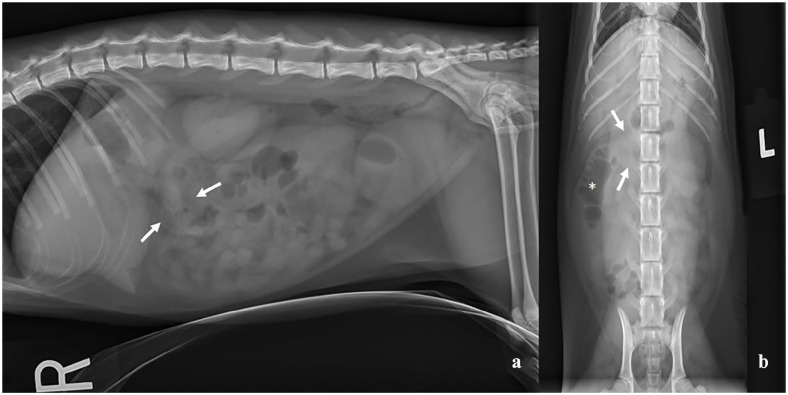

Case summary: A 5-month-old male castrated domestic shorthair cat was evaluated for acute onset of emesis. Abdominal radiographs identified a suspected colonic foreign body and abdominal-focused assessment with sonography for trauma, triage and tracking (AFAST) evaluation revealed a large amount of peritoneal effusion. Cytology of the peritoneal effusion was consistent with a septic exudate. An exploratory celiotomy identified a ruptured ileocecocolic mass and a resection and anastomosis was performed. No foreign material was identified and histopathology confirmed that the ruptured mass was a colonic duplication cyst. Recurrent septic peritonitis was diagnosed based on cytologic evaluation of fluid from a silicone bulb reservoir of a closed suction drain. No abnormalities were surgically identified, the cat recovered without complication, was discharged at 7 days postoperatively and has continued to remain healthy 8 months after surgical intervention.

Relevance and novel information: To our knowledge, this is the first known instance of a histopathologically confirmed non-communicating colonic duplication cyst causing septic peritonitis in the veterinary literature.